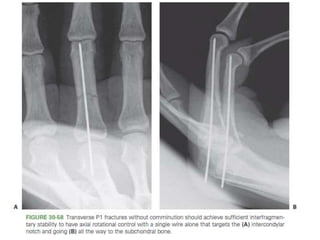

• #85 Figure 30-52 A: Unicondylar fractures of the head of P1 benefit from compression between the articular fragments through (B, C) lag screw fixation.

• #88  Figure 30-58 Transverse P1 fractures without comminution should achieve sufficient interfragmentary stability to have axial rotational control with a single wire alone that targets the (A) intercondylar notch and going (B) all the way to the subchondral bone.